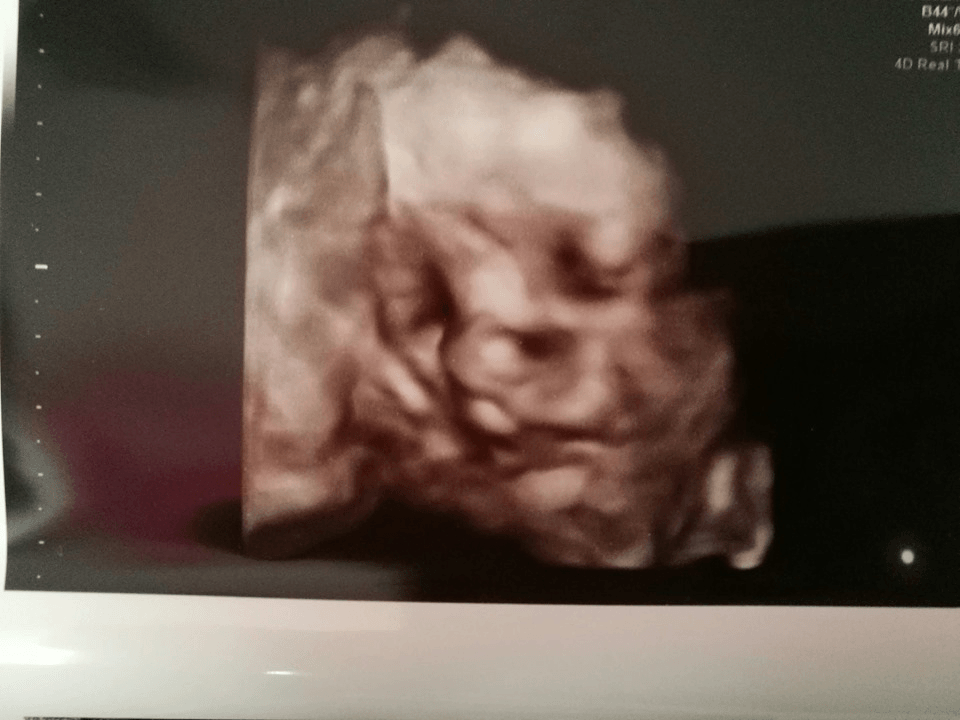

Też wam się pochwalę moją paskudnicą :)

Na 100% DrakuLaura będzie :p Obecna masa to 2 kg +/- na tych hadlockach widzę że ma od 1916 do 2248. Wiek płodu względem masy 32+3 czyli jest o jeden dzień młodsza niz wdl om :p

Łozysko nigdzie sobie nie poszło, siedzi z tyłu. II stopień dojrzałości. Laura leży glacą w dół

Zobacz załącznik 1050130

Super fotka🙂 zazdroszczę